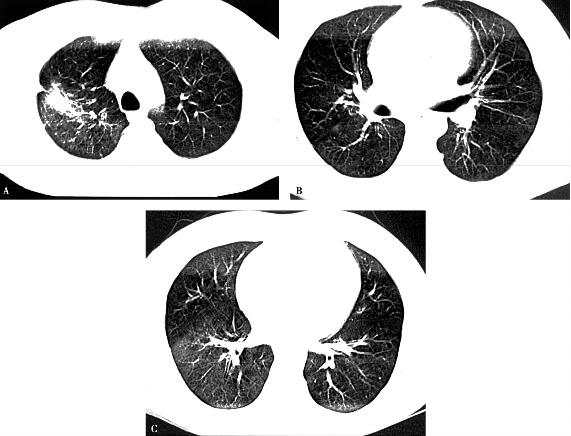

6.胸部影像学:右肺多叶、多段片状浸润性阴影,有实变,右胸腔有少量胸腔积液(图1)。

图1

具有临床意义的检查结果有:①血常规示白细胞计数、中性粒细胞百分比均增高; C-反应蛋白,降钙素原显著升高;②胸部影像学示右肺多发浸润影;③动脉血氧分压降低。结合患者的病史和体格检查结果,进一步支持感染性疾病—社区获得性肺炎(community acquired pneumonia,CAP)的诊断。动脉血氧分压降低考虑因肺部大面积炎性病变进而影响气体交换所致。进一步的处理应是立即选择合适的抗感染药物进行治疗。